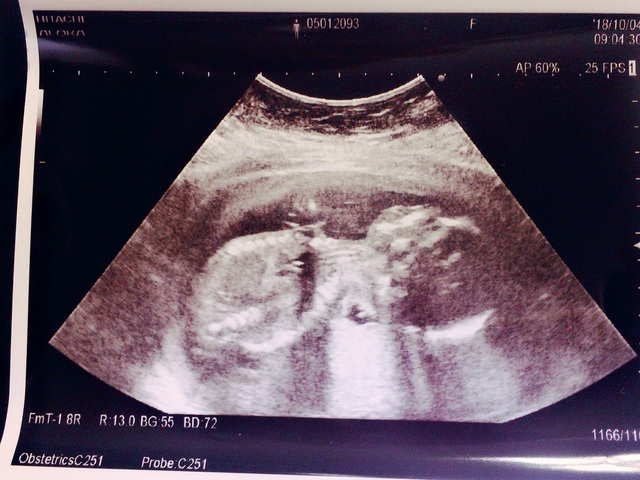

19週5日(19w5d・男の子)|グースケ さん(34歳)

エコー写真撮影時のエピソード:

里帰り出産にする予定で、実家の方の病院を受診した時に双子だと初めてわかりました。ビックリと同時に、二人とも元気で生まれてほしいと願っています。

双子は色々リスクがあるらしく、受診してエコーを撮るたびに二人が同じ様に成長してくれているかとても気になります。